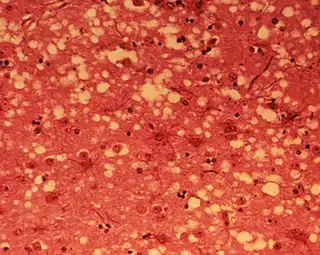

Los síntomas que se observan están motivados por la acumulación del prion en las células neuronales originando la muerte celular. Un análisis microscópico revela lesiones como vacuolas que dan al tejido nervioso un aspecto de esponja.